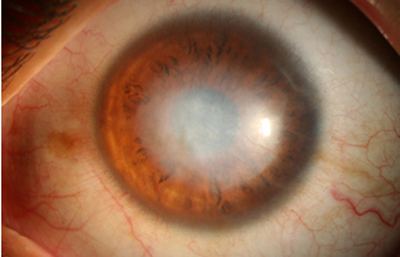

Superficie corneal irregular y grisácea, (Fig. 1, 2) con opácidades granulares en parche y formación de líneas epiteliales elevadas de aspecto granular (Fig. 3), que pueden arborizar dando imágenes de pseudodendritas. Opacidades superficiales satélites. (Figura 4) Inyección ciliar. Ulceración epitelial variante. (Figura 5).

Fig. 1 Síntomas de 15 días evolución